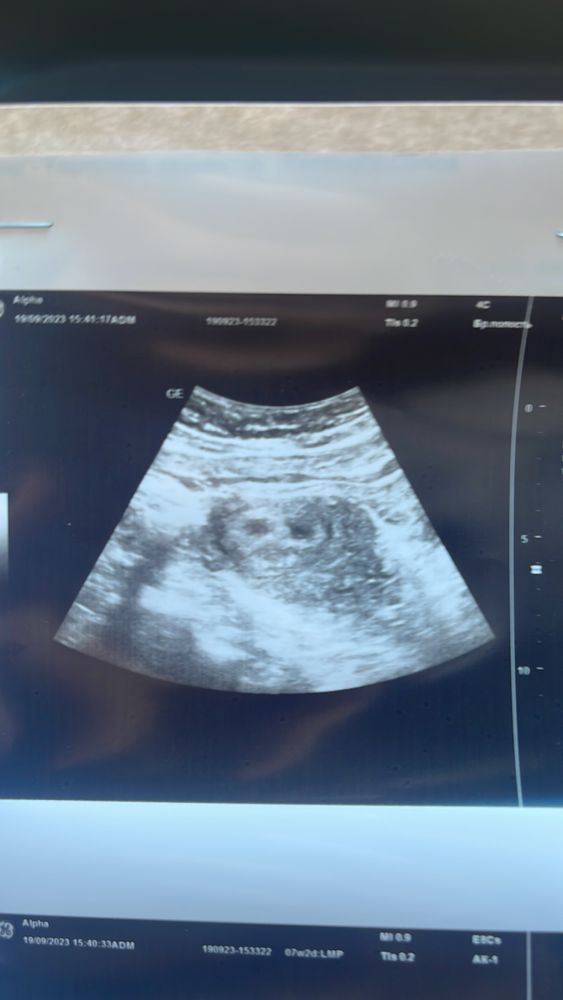

Двойня одно сердце(

У вас здесь стоит срок 9 недель. Наверное, это ошибка? По узи просто похоже на очень маленький срок. Если так, то всё нормально, сходите ещё раз через пару недель и уже будет всё понятно. Удачи вам!

Какой срок ?

Виктория, 5-6 недель поставили